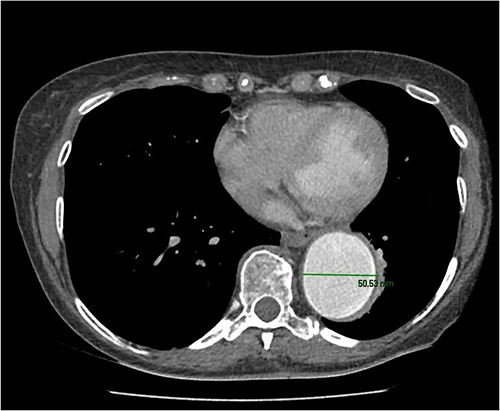

An 8 mm Gelweave graft was anastomosed to the left subclavian artery. Standard cannulation technique was used with the distal aorta and the right atrium. The distal aorta was sized and a 30/32 mm (15 cm length) Thoraflex graft was anastomosed with 4–0 prolene and reinforced with 1.5 cm Teflon. The supra-aortic vessels were reimplanted separately; deep hypothermia (20°C) was utilized for neuroprotection with antegrade cerebral perfusion and near infrared spectroscopy monitoring. Proximal aorta anastomosis followed patient rewarming. Her post-op CT aorta showed adequate perfusion and FET placement. A 3D reconstruction is shown in Figs 2 and 3. She was discharged on Day 10 and successful TEVAR was undertaken 8 months later (Fig. 4). Follow-up 24 months later showed no evidence of endoleak, stent migration or fracture.

3D reconstructed CT aorta image showing successful FET implantation at zone 0.